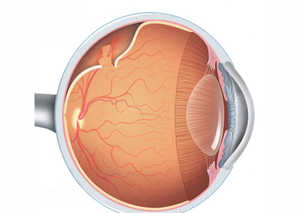

Вітреоретинальна хірургія є спеціалізованим напрямом офтальмологічної хірургії, який фокусується на лікуванні захворювань сітківки та склистого тіла. Цей вид хірургії включає в себе ряд складних операцій, які вимагають високої кваліфікації та сучасного обладнання. У Львів Медікал Центрі застосовуються передові методи вітреоретинальної хірургії для лікування різноманітних захворювань очей, забезпечуючи пацієнтам якісне відновлення зору.

Вітреоретинальна хірургія включає в себе різні хірургічні методи, спрямовані на лікування захворювань сітківки та склистого тіла. Ці процедури можуть бути необхідні при таких станах, як відшарування сітківки, макулярні дірки, епіретинальні мембрани, діабетична ретинопатія та інші складні захворювання очей.

Закрита вітректомія — це мікрохірургічна процедура, яка використовується для лікування захворювань та пошкоджень сітківки і скловидного тіла ока. Вона відноситься до видів операцій на задньому відділі ока.

Ревізія вітреоретинальної порожнини — це хірургічна процедура, яка виконується для огляду та лікування патологічних станів у порожнині ока, що включає скловидне тіло (вітреум) та сітківку (ретину).